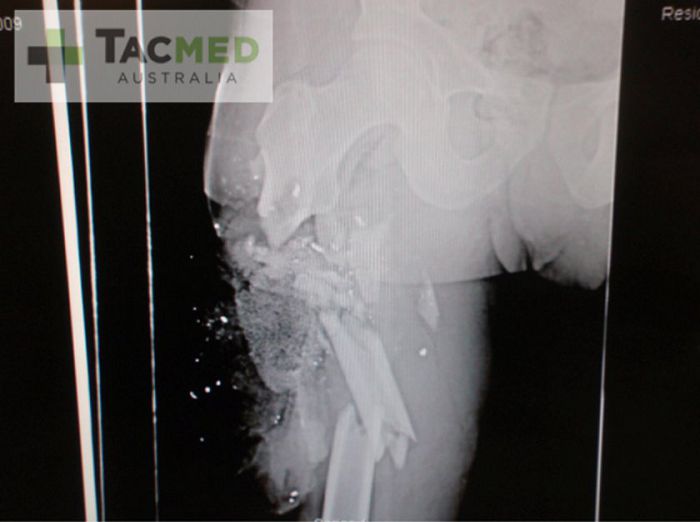

从上面这张照片你可以看出M4步枪的可怕威力,子弹从右臀下方进入并在右侧大腿部造成了巨大的创伤。下面这张X光片显示弹片穿透了大腿骨并将其完全击碎,碎裂的骨头刺进肌肉组织并构成了主要创伤。

瞬时空腔造成的压力效应也可以从第一张图中看出,巨大的淤青从臀部一直延伸到背部。这一淤青是由能量波冲击小血管造成的,巨大的冲击力将弹片经过部位的小血管震得粉碎。

X光片中的粉末状物体是老一代QuikClot牌高级凝血绵,这种物质能够将内出血控制到最低程度。另外图中的高亮白色碎片就是弹片小块,由子弹击中人体组织及骨骼后解体产生。子弹碎片也是M4枪伤的可怕之处,带有一定速度的弹片在人体组织中解体可不是什么好受的事情。